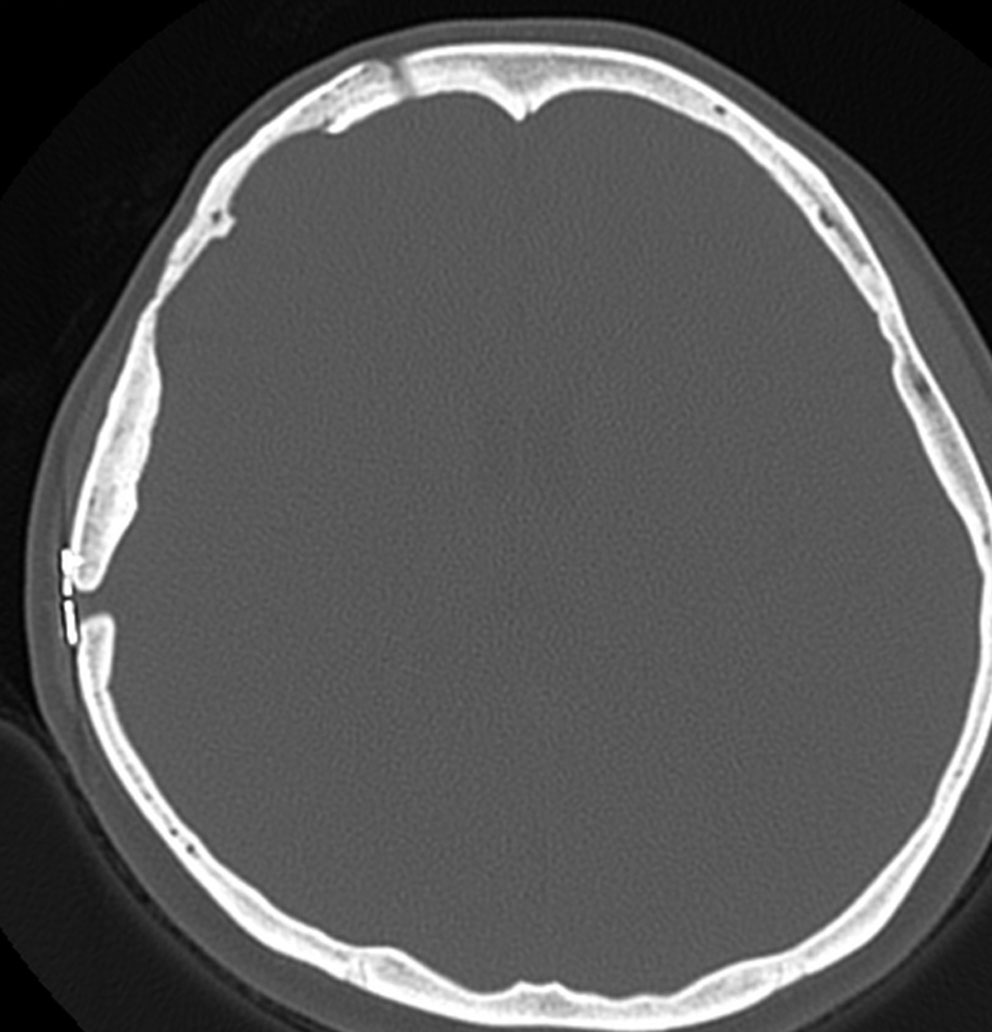

骨内髄膜腫 osseous meningioma

骨内増殖をする髄膜腫です。頭蓋骨腫瘍と間違えるようなものです。触った感じは骨腫ですが,CTでは,表面が毛羽立っていて,頭蓋冠に浸潤していることが特徴です。浅側頭動脈からの豊富な血流があります。

わずかですが頭蓋内にも腫瘍があり,硬膜が肥厚してガドリニウム増強されます。

頭蓋骨をかなり広範におかすので骨は捨てません。開頭して取り外した骨の厚くなっている部分と髄膜腫で軟らかくなっている部分を削除して,それから骨片をオートクレーブで短時間熱処理して,元あった所にもどします。下の画像は手術後1年半が経過したものですが,髄膜腫の再発はなく,熱処理骨弁は吸収されないで生着しています。